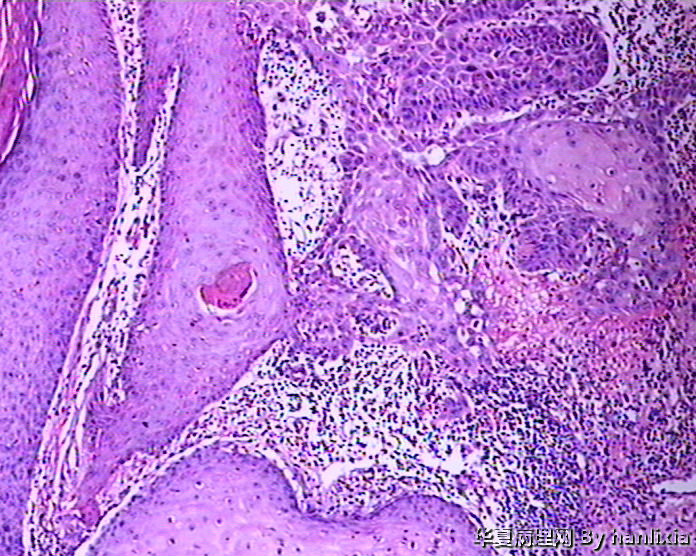

男性患者,50岁,发现面部皮肤(耳旁)肿物一年余,色黑。

高分化鳞状细胞癌

高分化鳞癌可能,也可能AK基础上发展而来的浅表型鳞癌?

部分区域突破基底膜,应该诊断鳞癌,由日光性角化发展过来的!